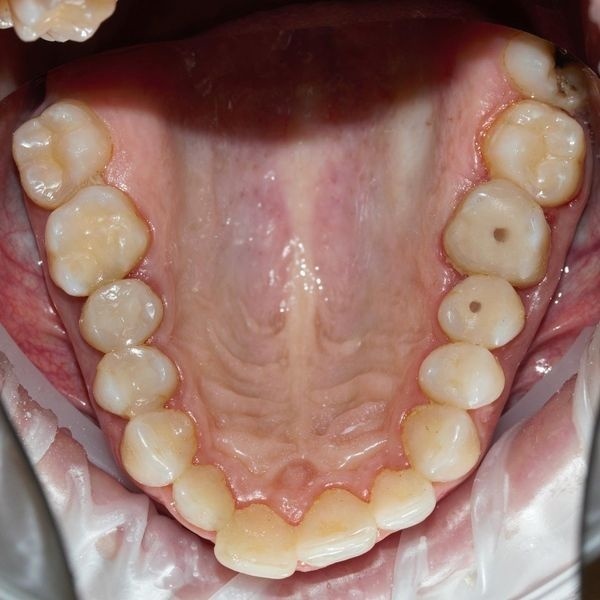

По результатам зондирования:

- инструмент застревал и вызывал сильную боль;

- десна кровоточила;

- между десной и зубами образовались патологические карманы.

3D-томография показала:

- кариес под пломбами находился глубоко;

- нервы располагались близко к кариесу;

- между жевательными зубами и десной образовались карманы по 2–4 мм;

- корни зубов не разрушены.